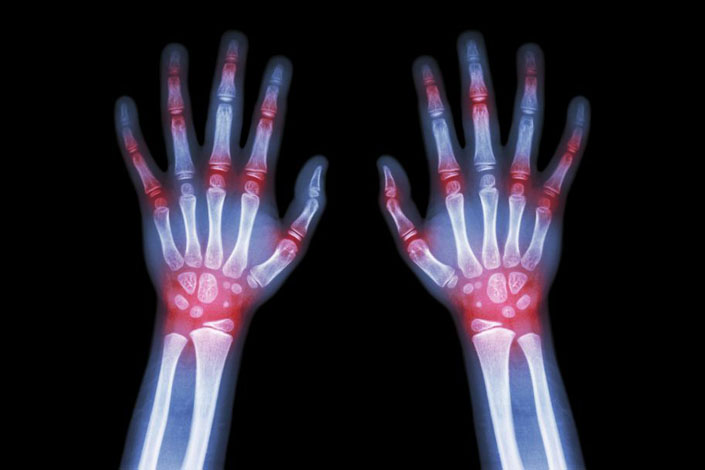

Choroby reumatyczne – olbrzymie opóźnienia w diagnostyce

W Polsce opóźnienia diagnostyczne w chorobach reumatycznych bywają ogromne. W reumatoidalnym zapaleniu stawów (RZS) wynoszą ok. trzech lat, w ZZSK czy łuszczycowym zapaleniu…